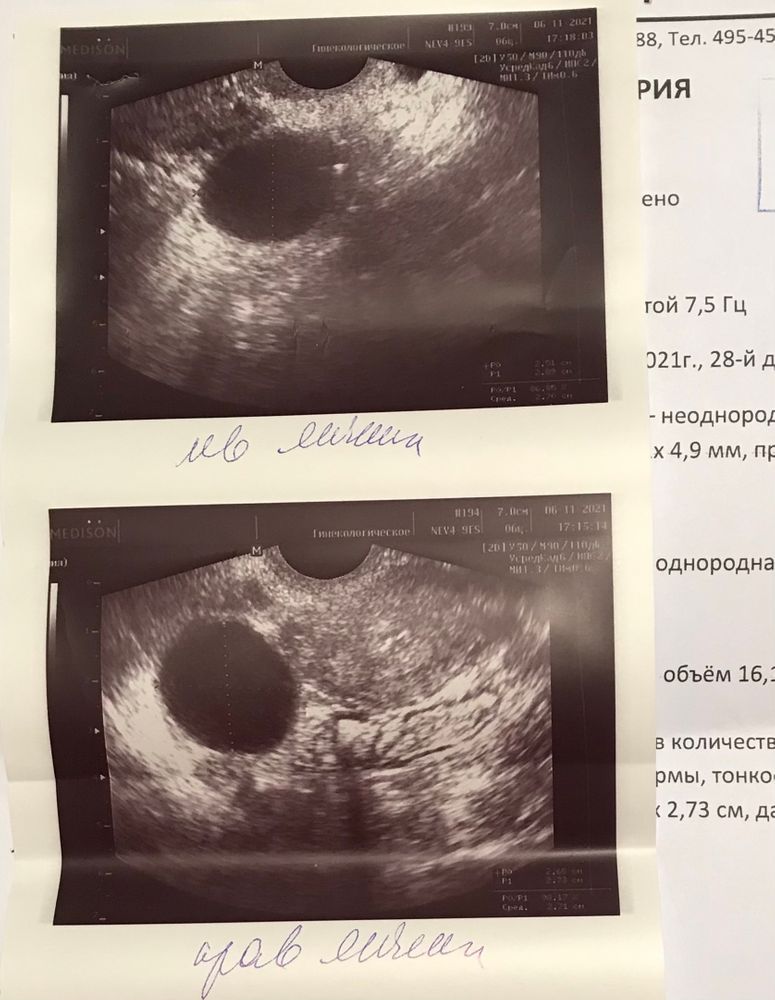

Девочки, привет. Сегодня (предположительно) 29й ДЦ. Предположительно, потому что первые месячные после родов были 10 окт и довольно скудные.. тест показал овулю на 22 ДЦ, были все признаки: повышенное либидо, ЯБ, тянущие боли внизу живота. И вот вчерашнее узи фолликулометрия 😔 никакой овуляции и симметричные образования в обоих яичниках по 2 с лишним см и с каким-то кровотоком. Слева болит :( Может ли быть такое, что организм подавал «ложные» сигналы об овуляции? Раньше всегда овуляция вовремя и ощущения те же были.. к врачу, конечно, схожу. Всем спасибо заранее за ответы